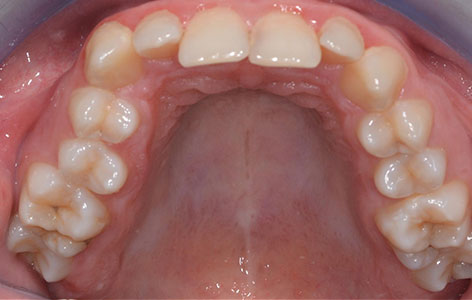

Este un aparat fix adițional, care este utilizat atunci când maxilarul este mult îngustat, rolul său fiind acela de a expansiona rapid arcada superioară pentru a face spațiu unor dinți sau pentru a corespunde cu arcada inferioară. Întotdeauna acest aparat este urmat de un aparat fix clasic care va continua alinierea dintilor in spatiul creat și definitivarea ocluziei corecte. Disjunctorul se cimentează pe molari si premolari, având partea activă reprezentată de un șurub median imediat sub bolta palatină.